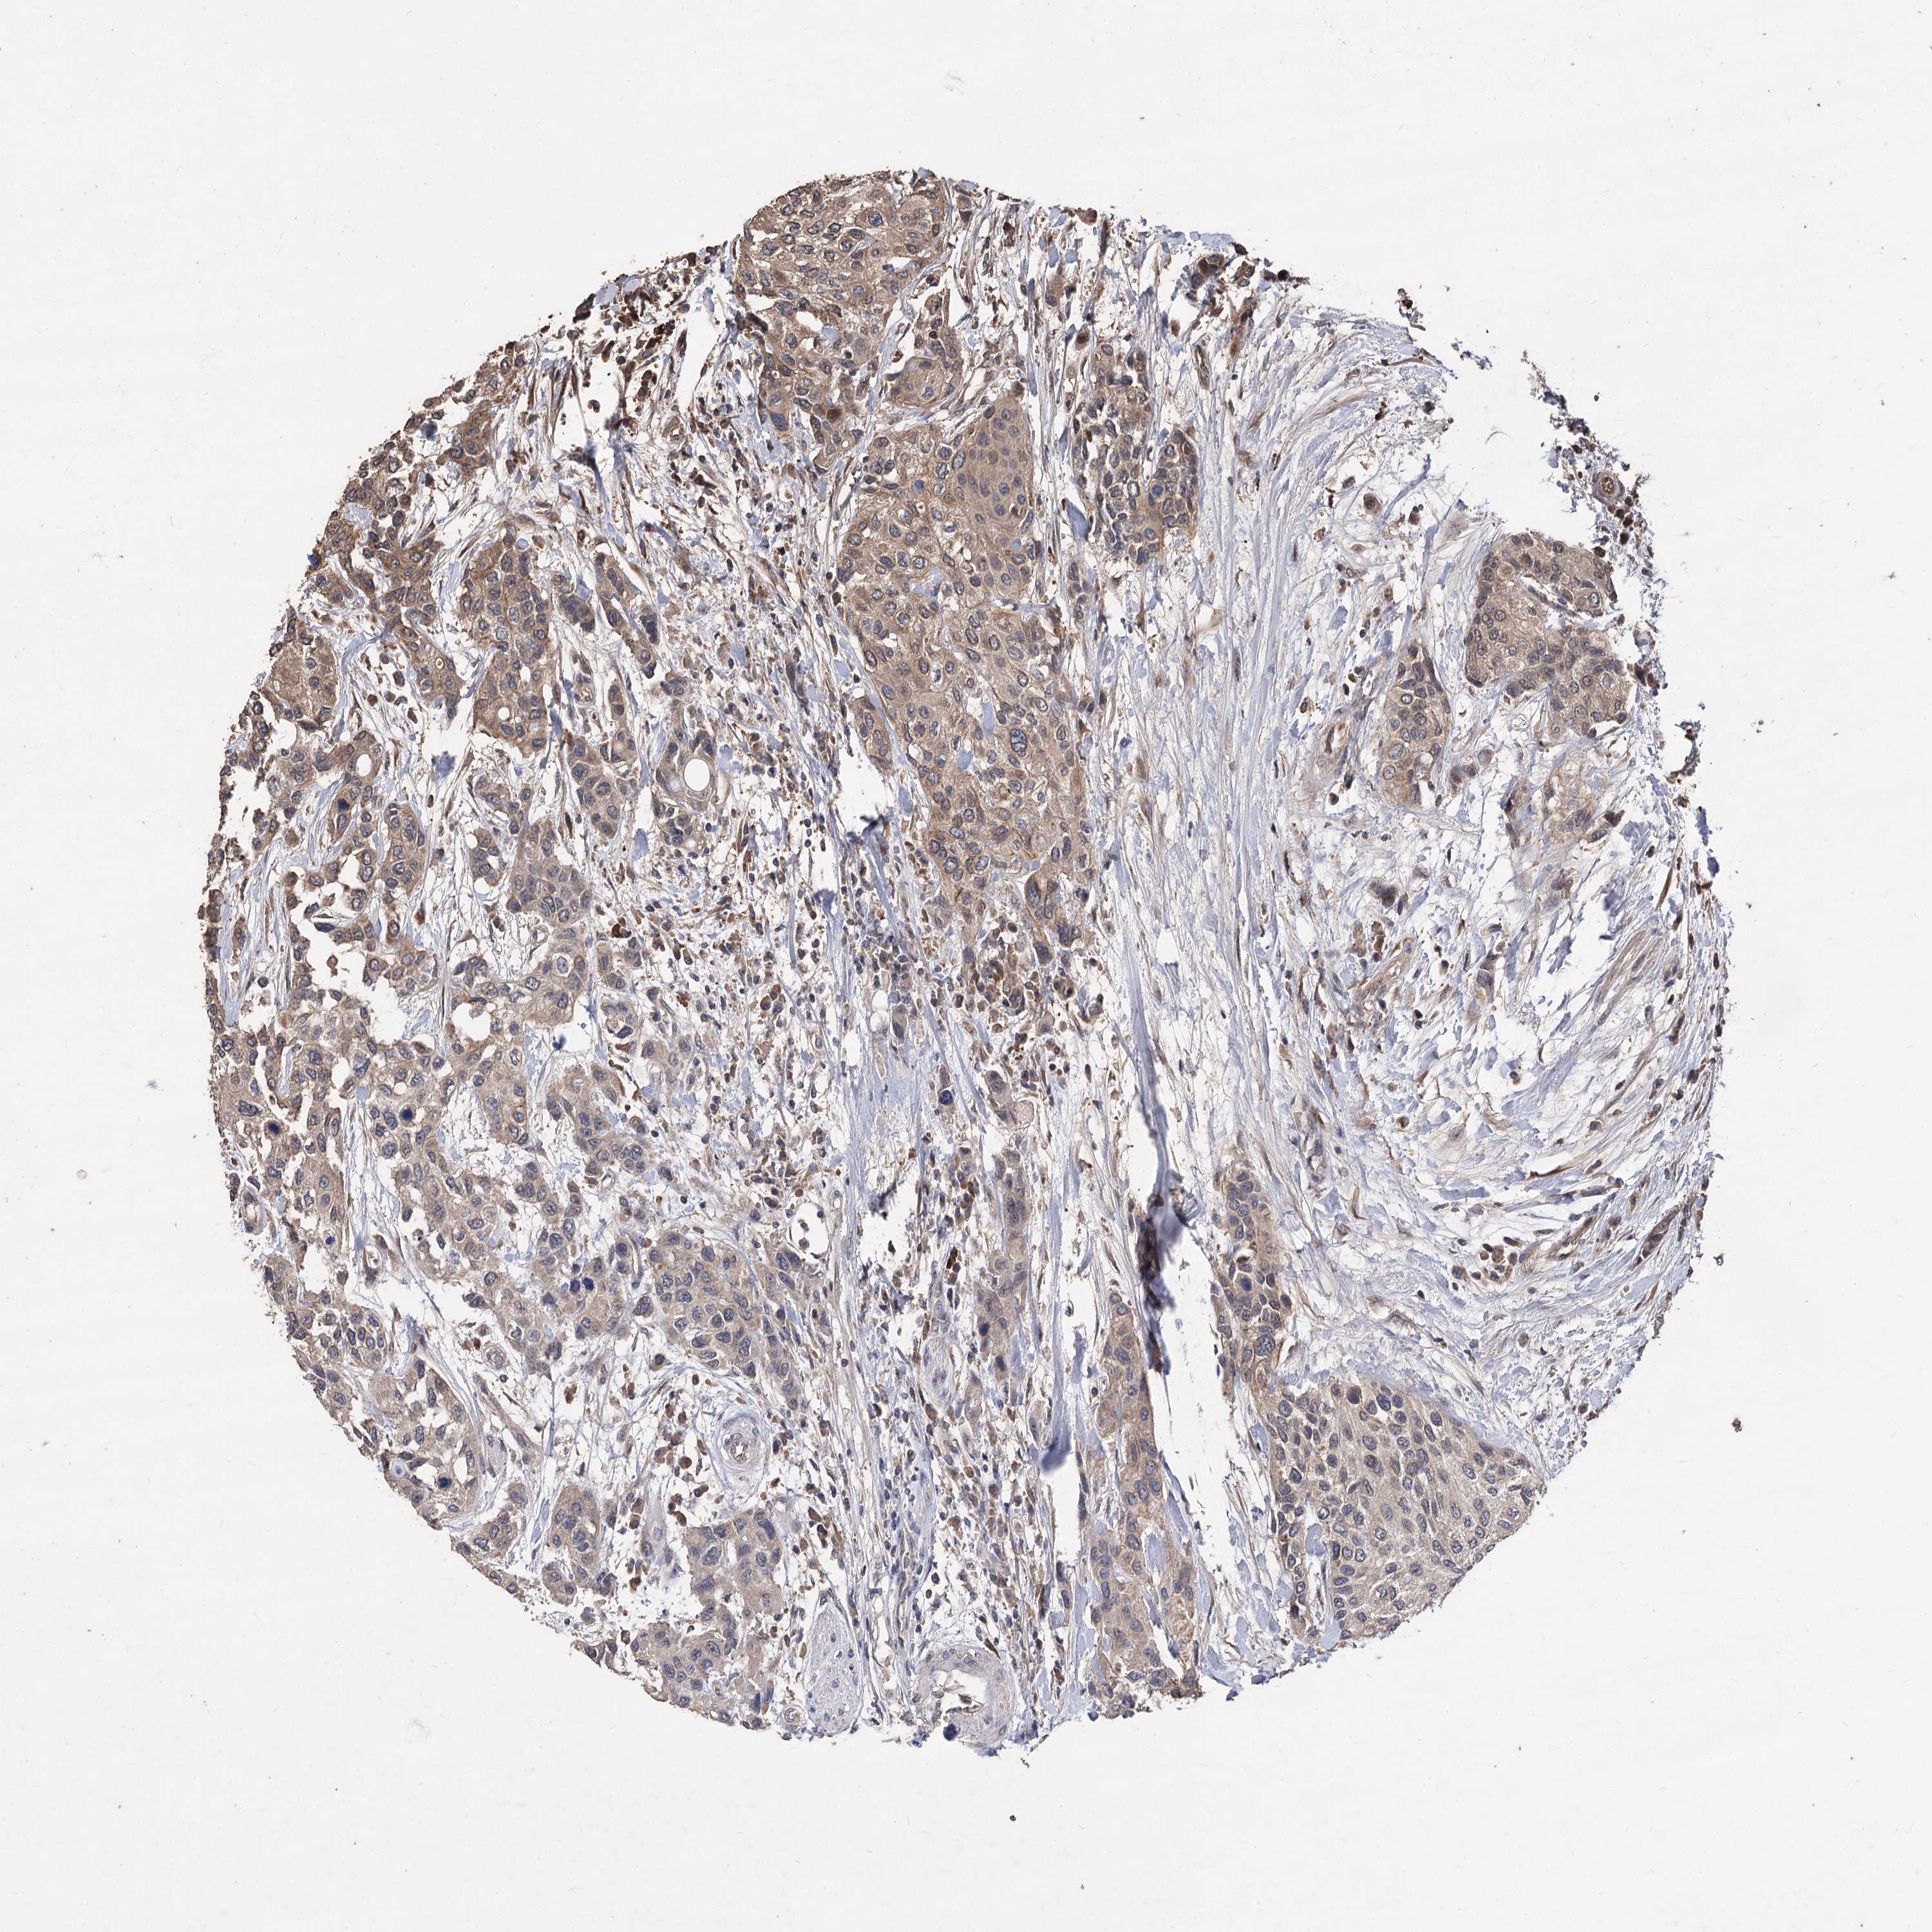

UROTHELIAL CANCER - Protein expressioni

A mouse-over function shows sample information and annotation data. Click on an image to view it in a full screen mode. Samples can be filtered based on level of antibody staining by selecting one or several of the following categories: high, medium, low and not detected. The assay and annotation is described here.

Note that samples used for immunohistochemistry by the Human Protein Atlas do not correspond to samples in the TCGA dataset.

Antibody stainingi

Antibody staining in the annotated cell types in the current human tissue is reported as not detected, low, medium, or high, based on conventional immunohistochemistry profiling in selected tissues. This score is based on the combination of the staining intensity and fraction of stained cells.

Each image is clickable and will lead to virtual microscopy that enables deeper exploration of all samples and also displays staining intensity scores, fraction scores and subcellular localization as well as patient and tissue information for each sample.

Antibody HPA038469

Antibody CAB022664

Antibody CAB034035

Staining

High

Medium

Low

Not detected

Intensity

Strong

Moderate

Weak

Negative

Quantity

>75%

75%-25%

<25%

None

Location

Nuclear

Cytoplasmic/membranous

Cytoplasmic/membranous,nuclear

Urothelial carcinoma, High grade

Urothelial carcinoma, Low grade